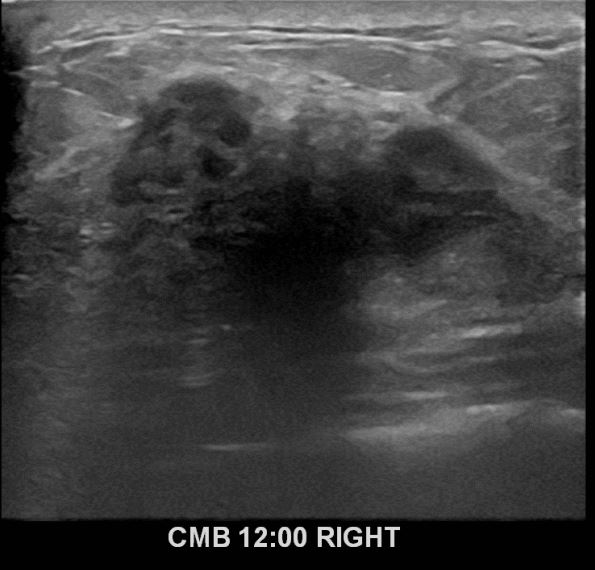

아산유외과 개원후 638번째유방암진단

상기환자 외부검사상 이상소견으로 내원하신 50대여성으로 우측 유방의 의심스러혹

조직검사시행해 유방암 진단되었읍니다